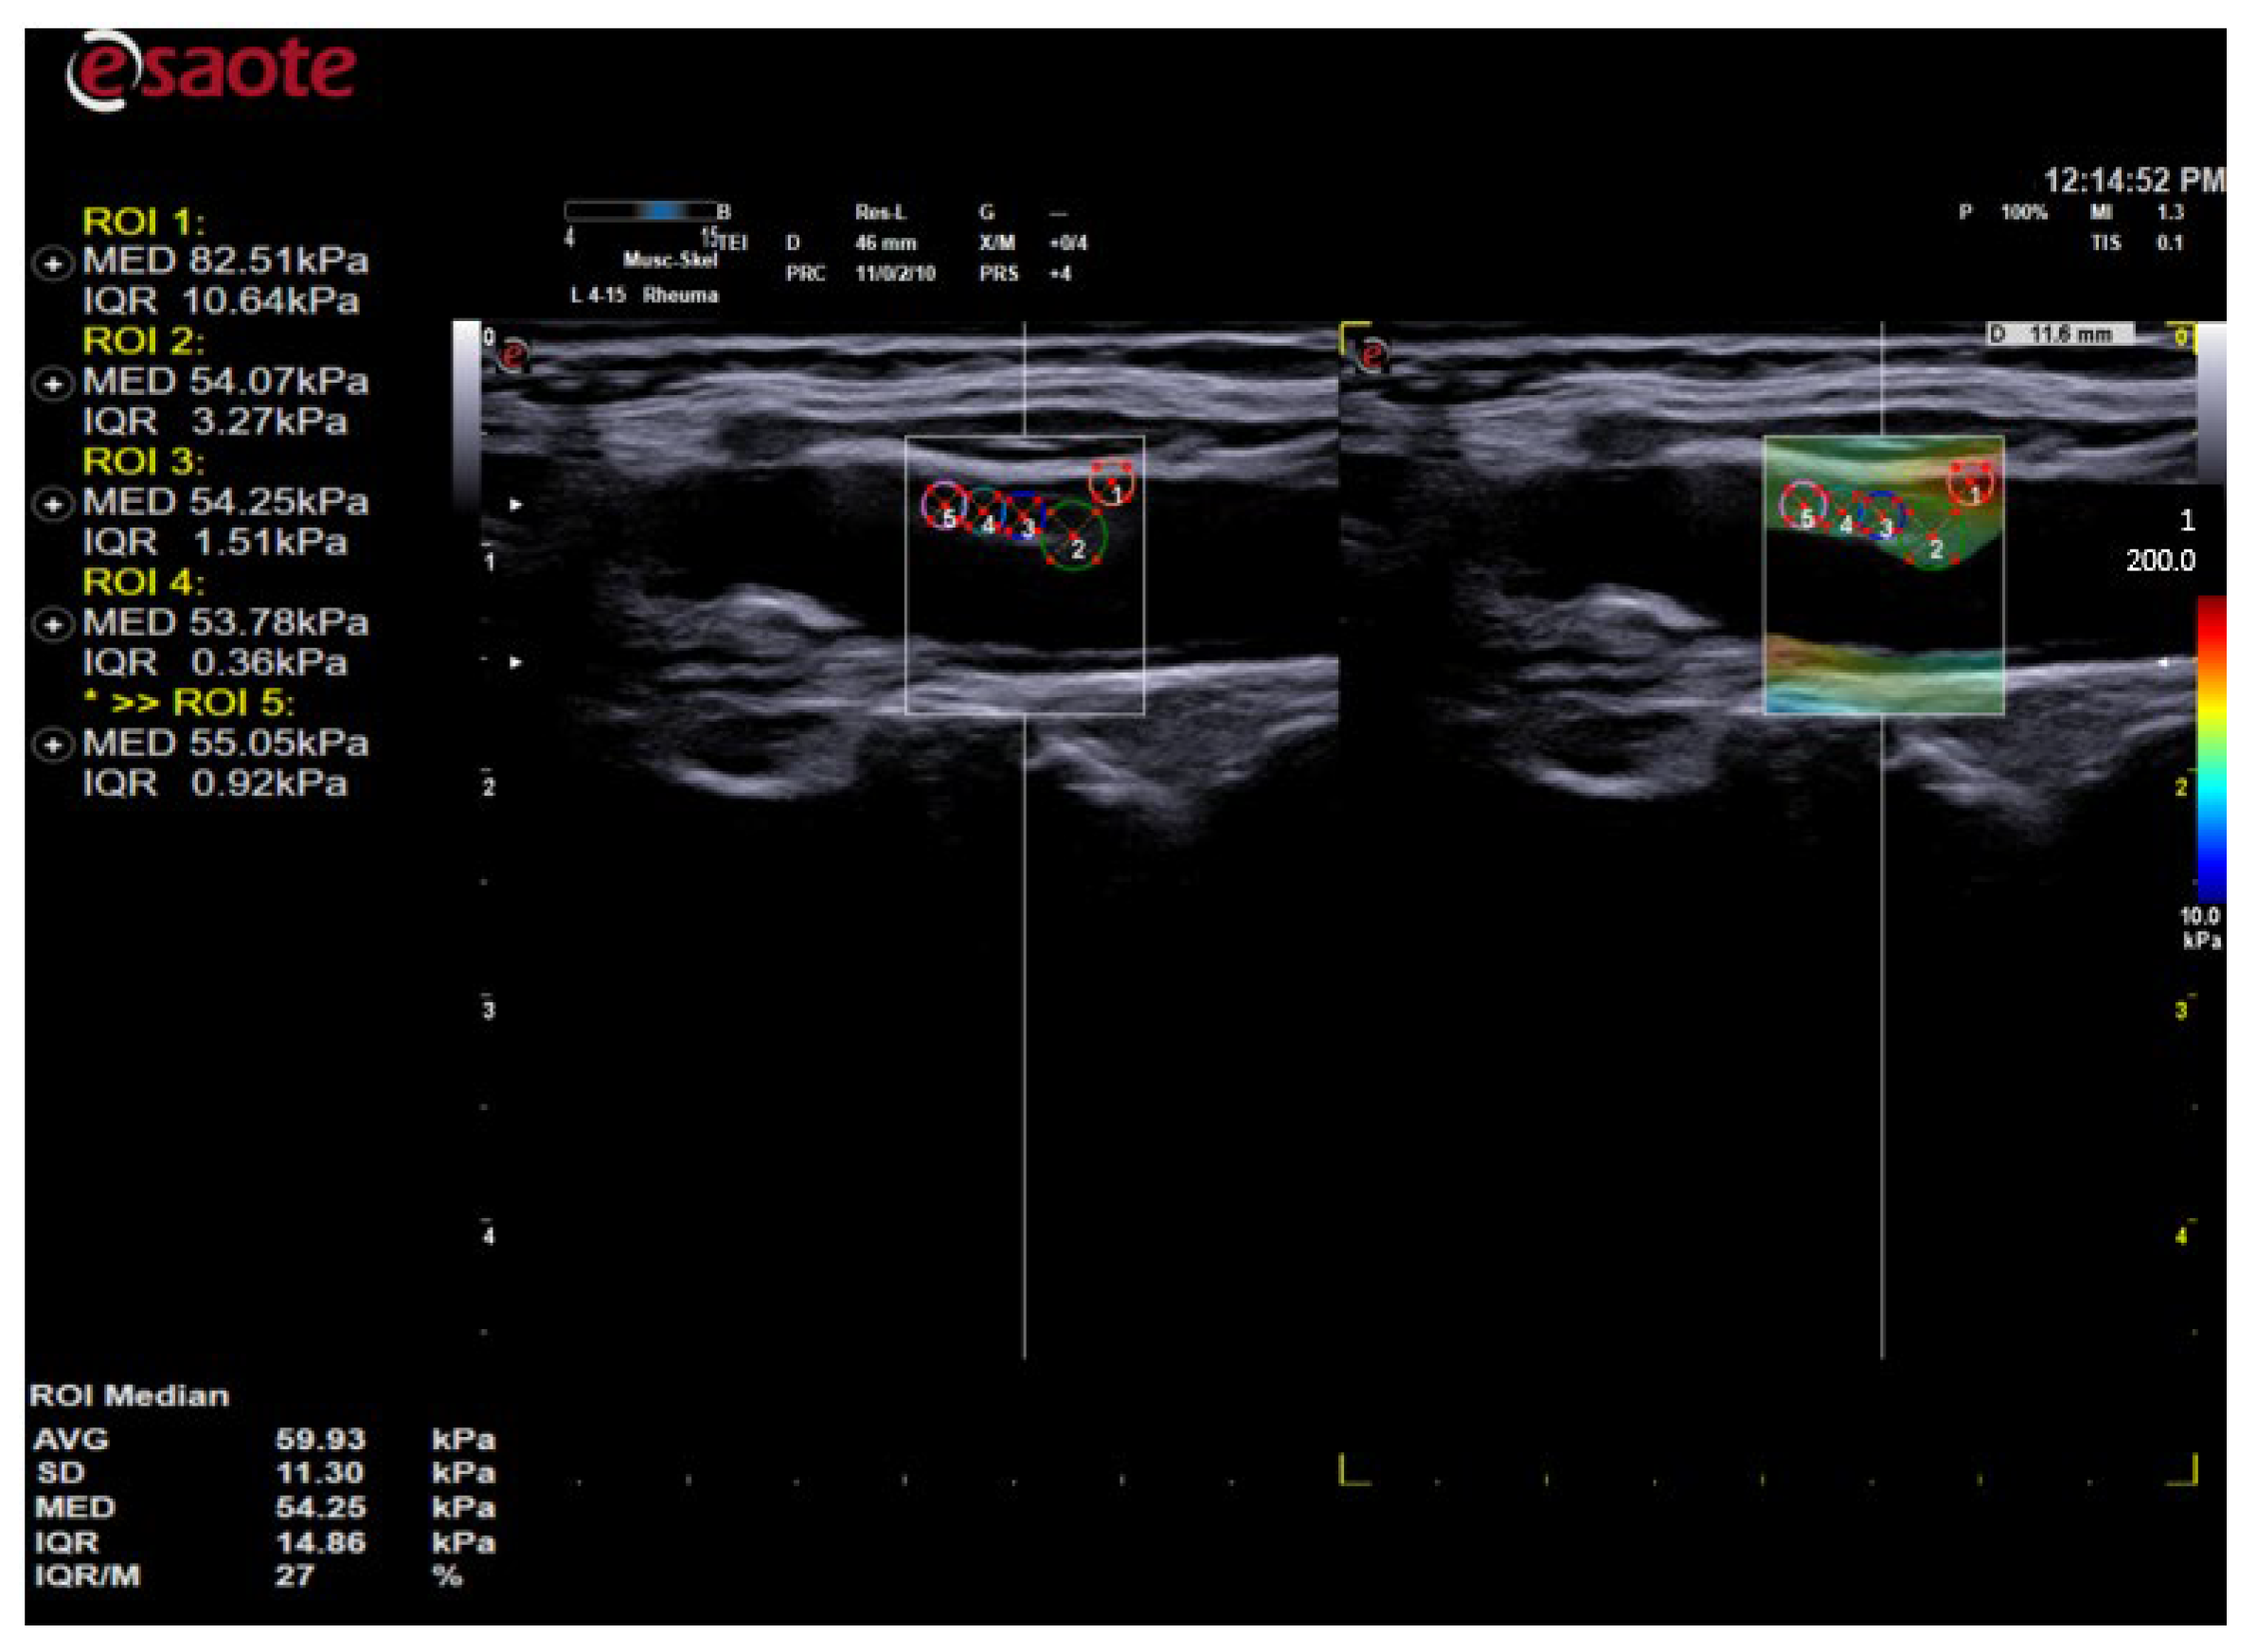

- The maximum stiffness of the elastogram correlating with the red color and values up to 200 kPa;

- The minimum value being that of blood, which was used to compare the soft structures in blue color (0 kPa);

- Frequency of SWE frames at 1 Hz;

- Processing power and frames per second: 10 frames per second.